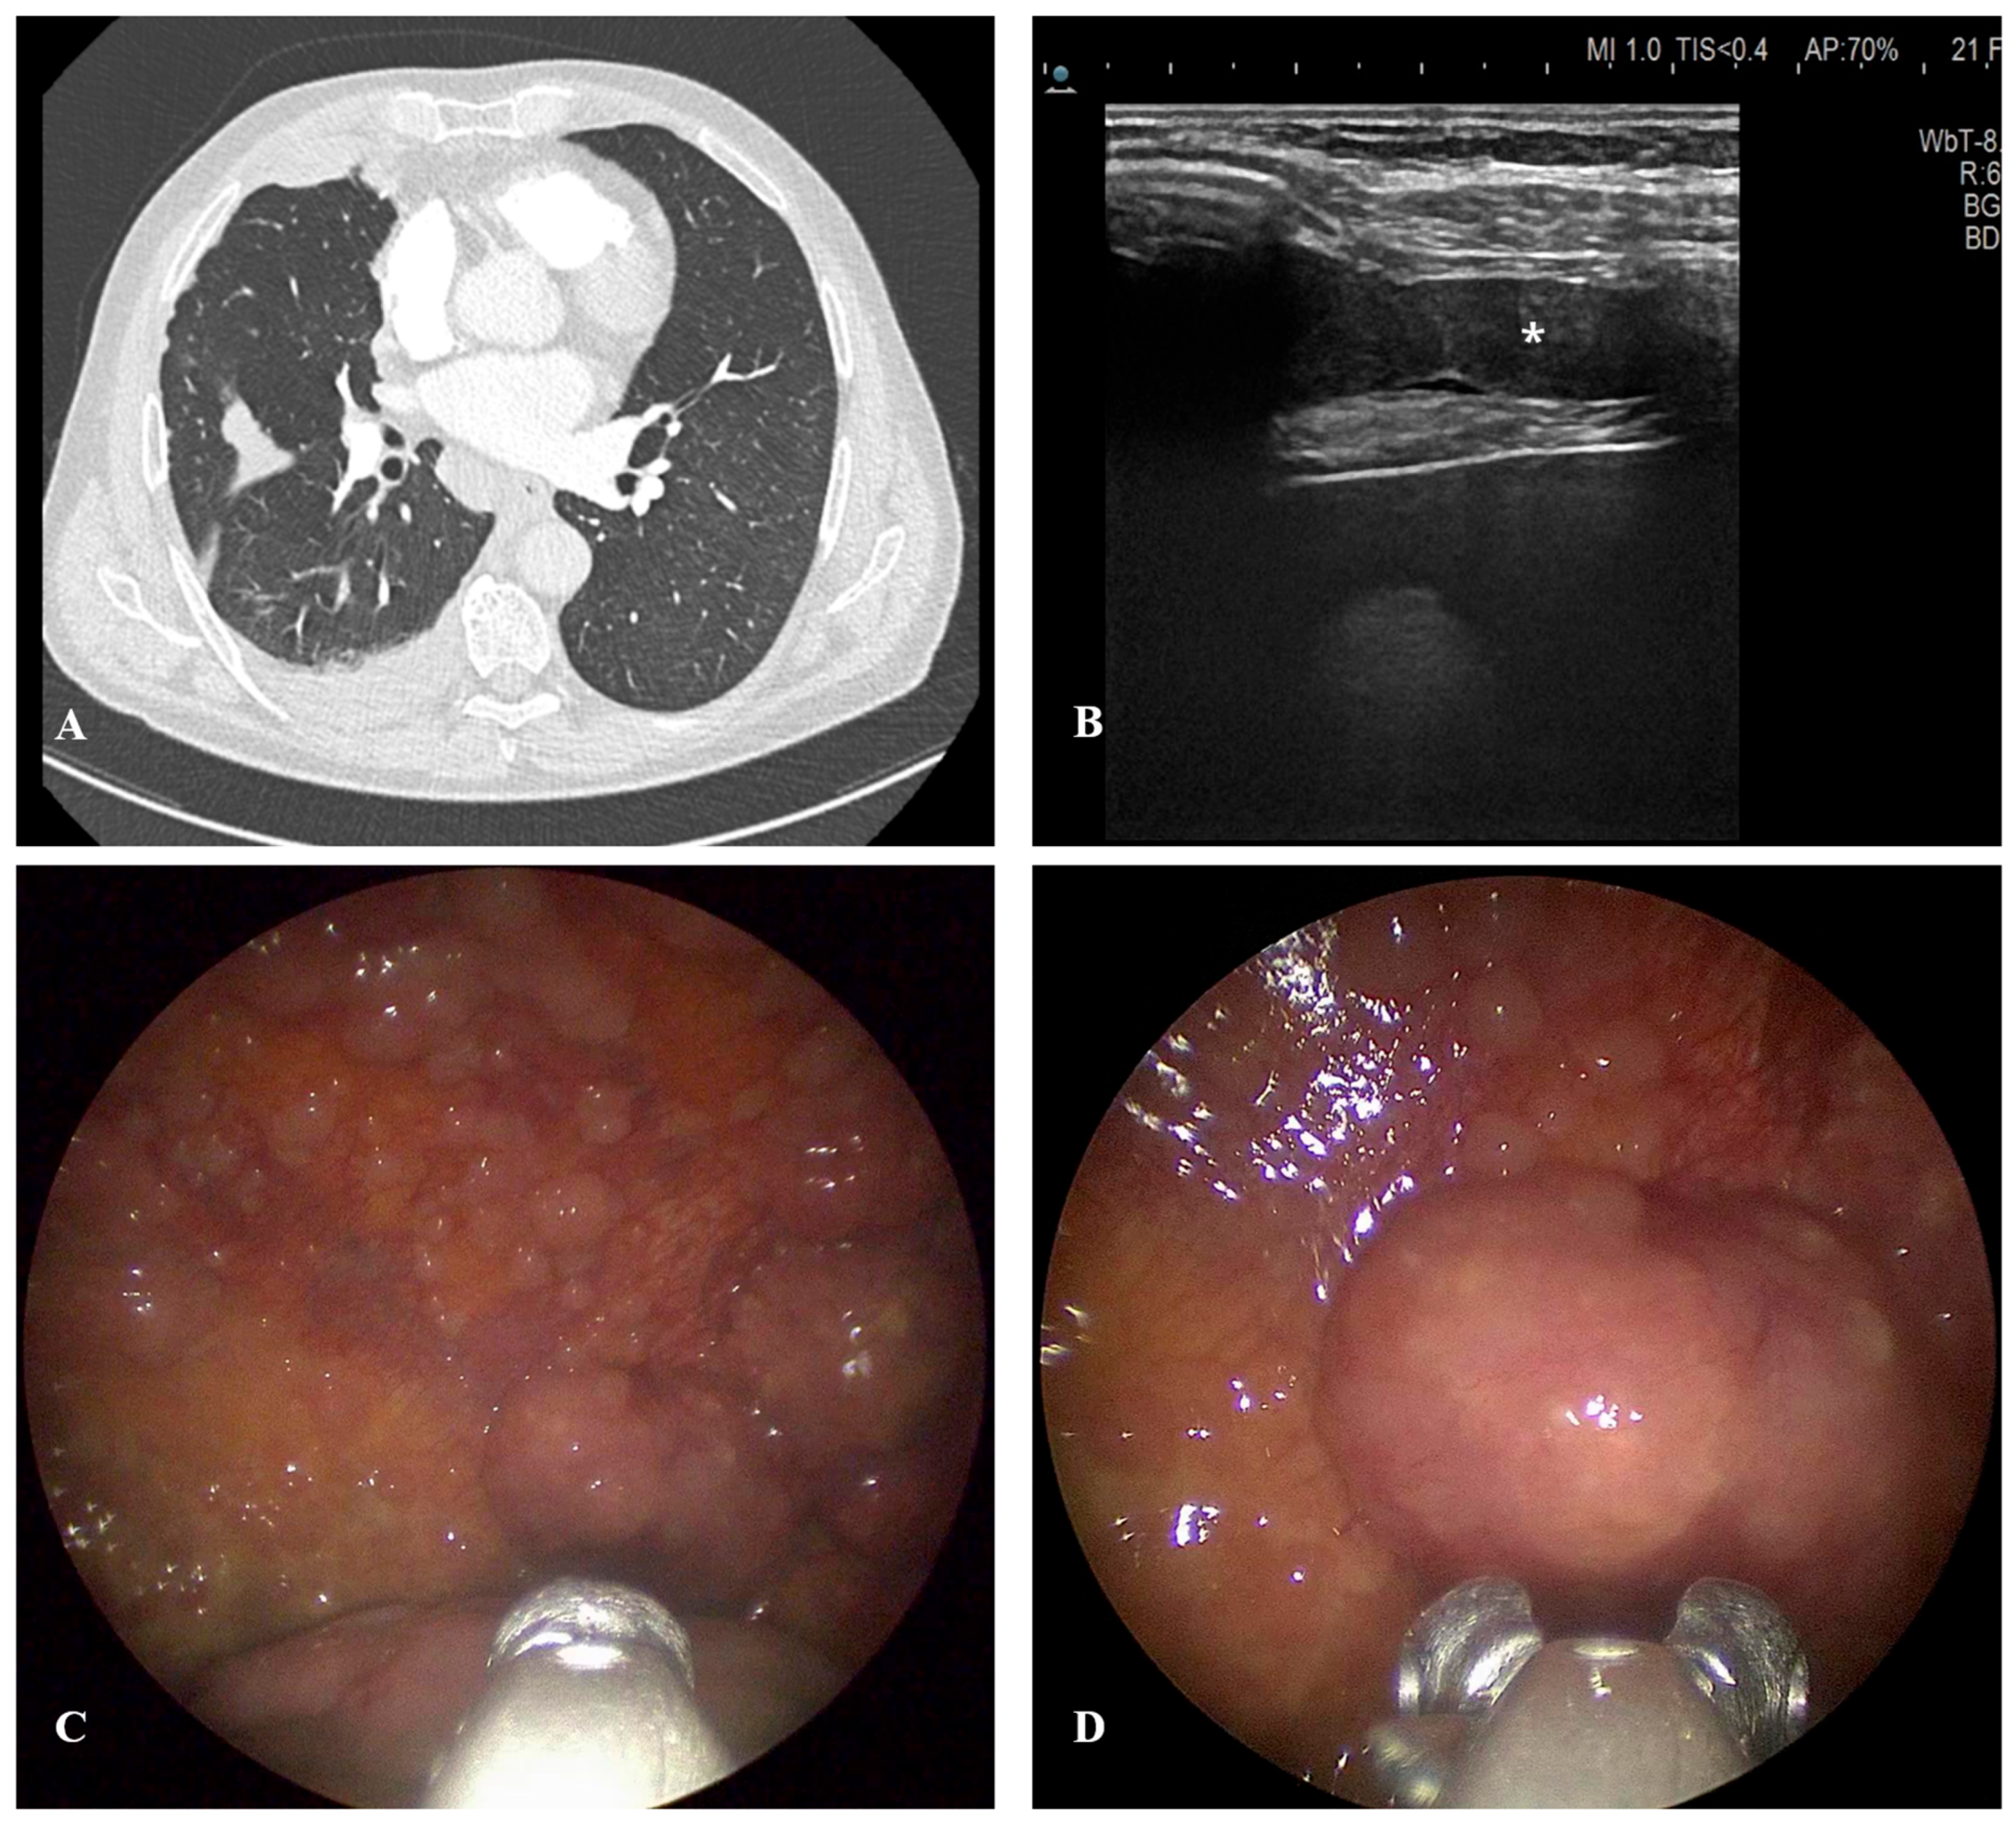

5.3. Computed Tomography

5.2. Thoracic Ultrasound

6.3. Medical Thoracoscopy